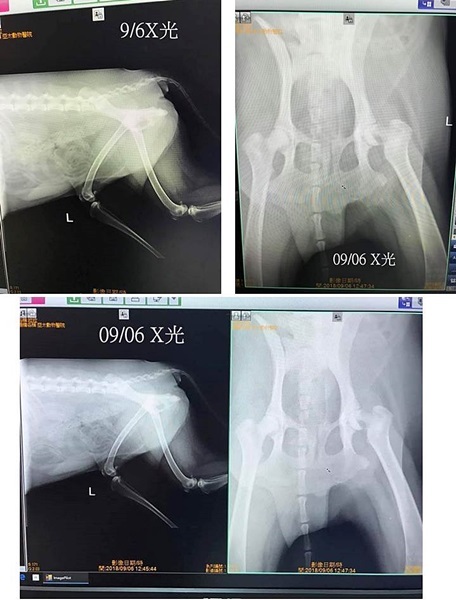

X光檢驗左後腿股骨骨折,手術切除斷裂的骨頭,

醫師診斷,依拉拉的年紀應軟骨可自行生長,日後行走應可恢復到六七成,

且需注意飲食均衡,因檢查發現拉拉的骨質結構較差,要藉由飲食吸收去改善。